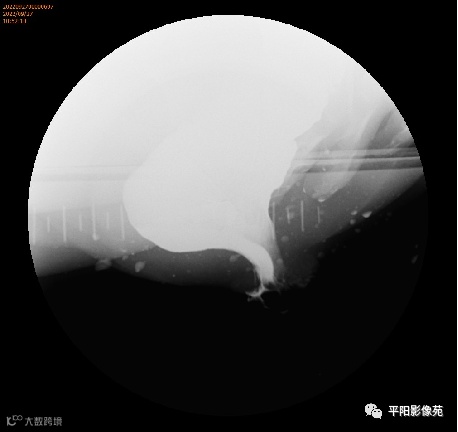

排粪造影

直肠壁部分或全层向下移位,称为直肠脱垂(rectal prolapse)

直肠壁部分下移,即直肠黏膜下移,称黏膜脱垂或不完全脱垂

直肠壁全层下移称完全脱垂

排便造影钡(x射线)排便造影或排便直肠造影是诊断排便障碍的公认临床

钡排粪造影实时评估直肠壁形态、盆底运动和排空。